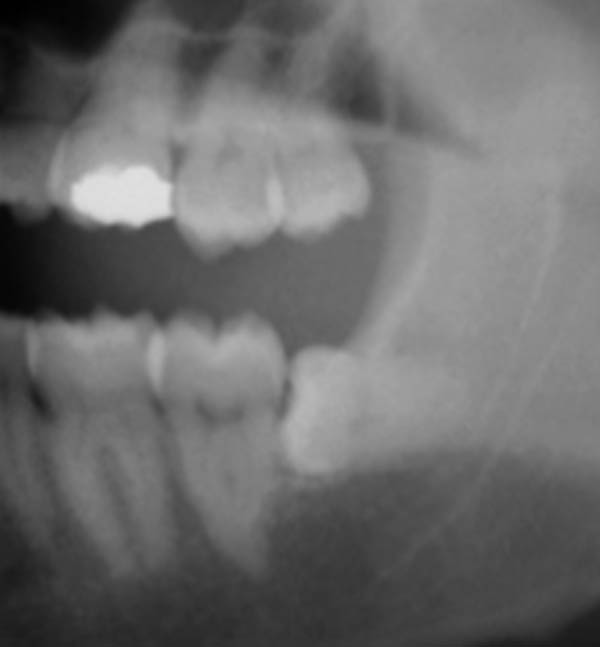

Mr Kumar is regularly referred patients with jaw joint problems. In most cases, this disorder is conservatively managed through jaw exercises, soft diet, use of bite splints or medication with only rare cases requiring surgery.

Soft Bite Raising Appliance